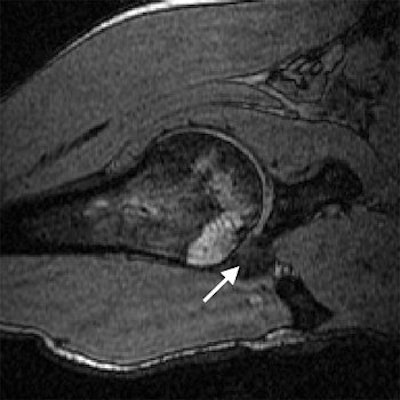

| Transverse 3D gradient-echo MR images (30/10) with volunteer in neutral position (above), unloaded ABER position at 90° external rotation (middle), and 111° external rotation (below). Note infraspinatus tendon (arrow) deformed between the greater tuberosity and posterosuperior glenoid in the loaded study. |

Based on the image evaluation, contact was observed between the supraspinatus and the posterosuperior glenoid in the unloaded and loaded ABER positions in all eight volunteers. Again, in all eight subjects, contact was noted between the infraspinatus near the insertion and posterior glenoid in the loaded and unloaded positions. Four cases were deemed grade 2. Intraobserver agreement between the two radiologists on supraspinatus and infraspinatus tendon contact with the glenoid was excellent (k = 0.875).

The researchers also assessed minimum distances and noted changes in distance in the loaded ABER position. They found that the minimum distance between the supraspinatus insertion and the acromion dipped from 16.9 mm to 5.7 mm, while the infraspinatus to glenoid distance went from 38.4 mm to 3.6 mm. The supraspinatus to glenoid distance went from 35 mm to 6.6 mm. Finally, the distance between the greater tuberosity and glenoid decreased from 21.5 mm to 3.6 mm.

This last result suggested that "a larger portion of the greater tuberosity (including the supraspinatus and infraspinatus insertions) may be important in the minimum distance measurement," the authors stated. "The infraspinatus insertion, in particular, came to within 3.6 mm from the glenoid, on average."

The group came up with a couple of recommendations based on the results. First, a decrease in minimum distance may not translate directly to clinical impingement because contact between the rotator cuff and glenoid occurs even in asymptomatic individuals during the loaded ABER position. Also, the loaded position may be more specific for internal, rather than subacromial, impingement.